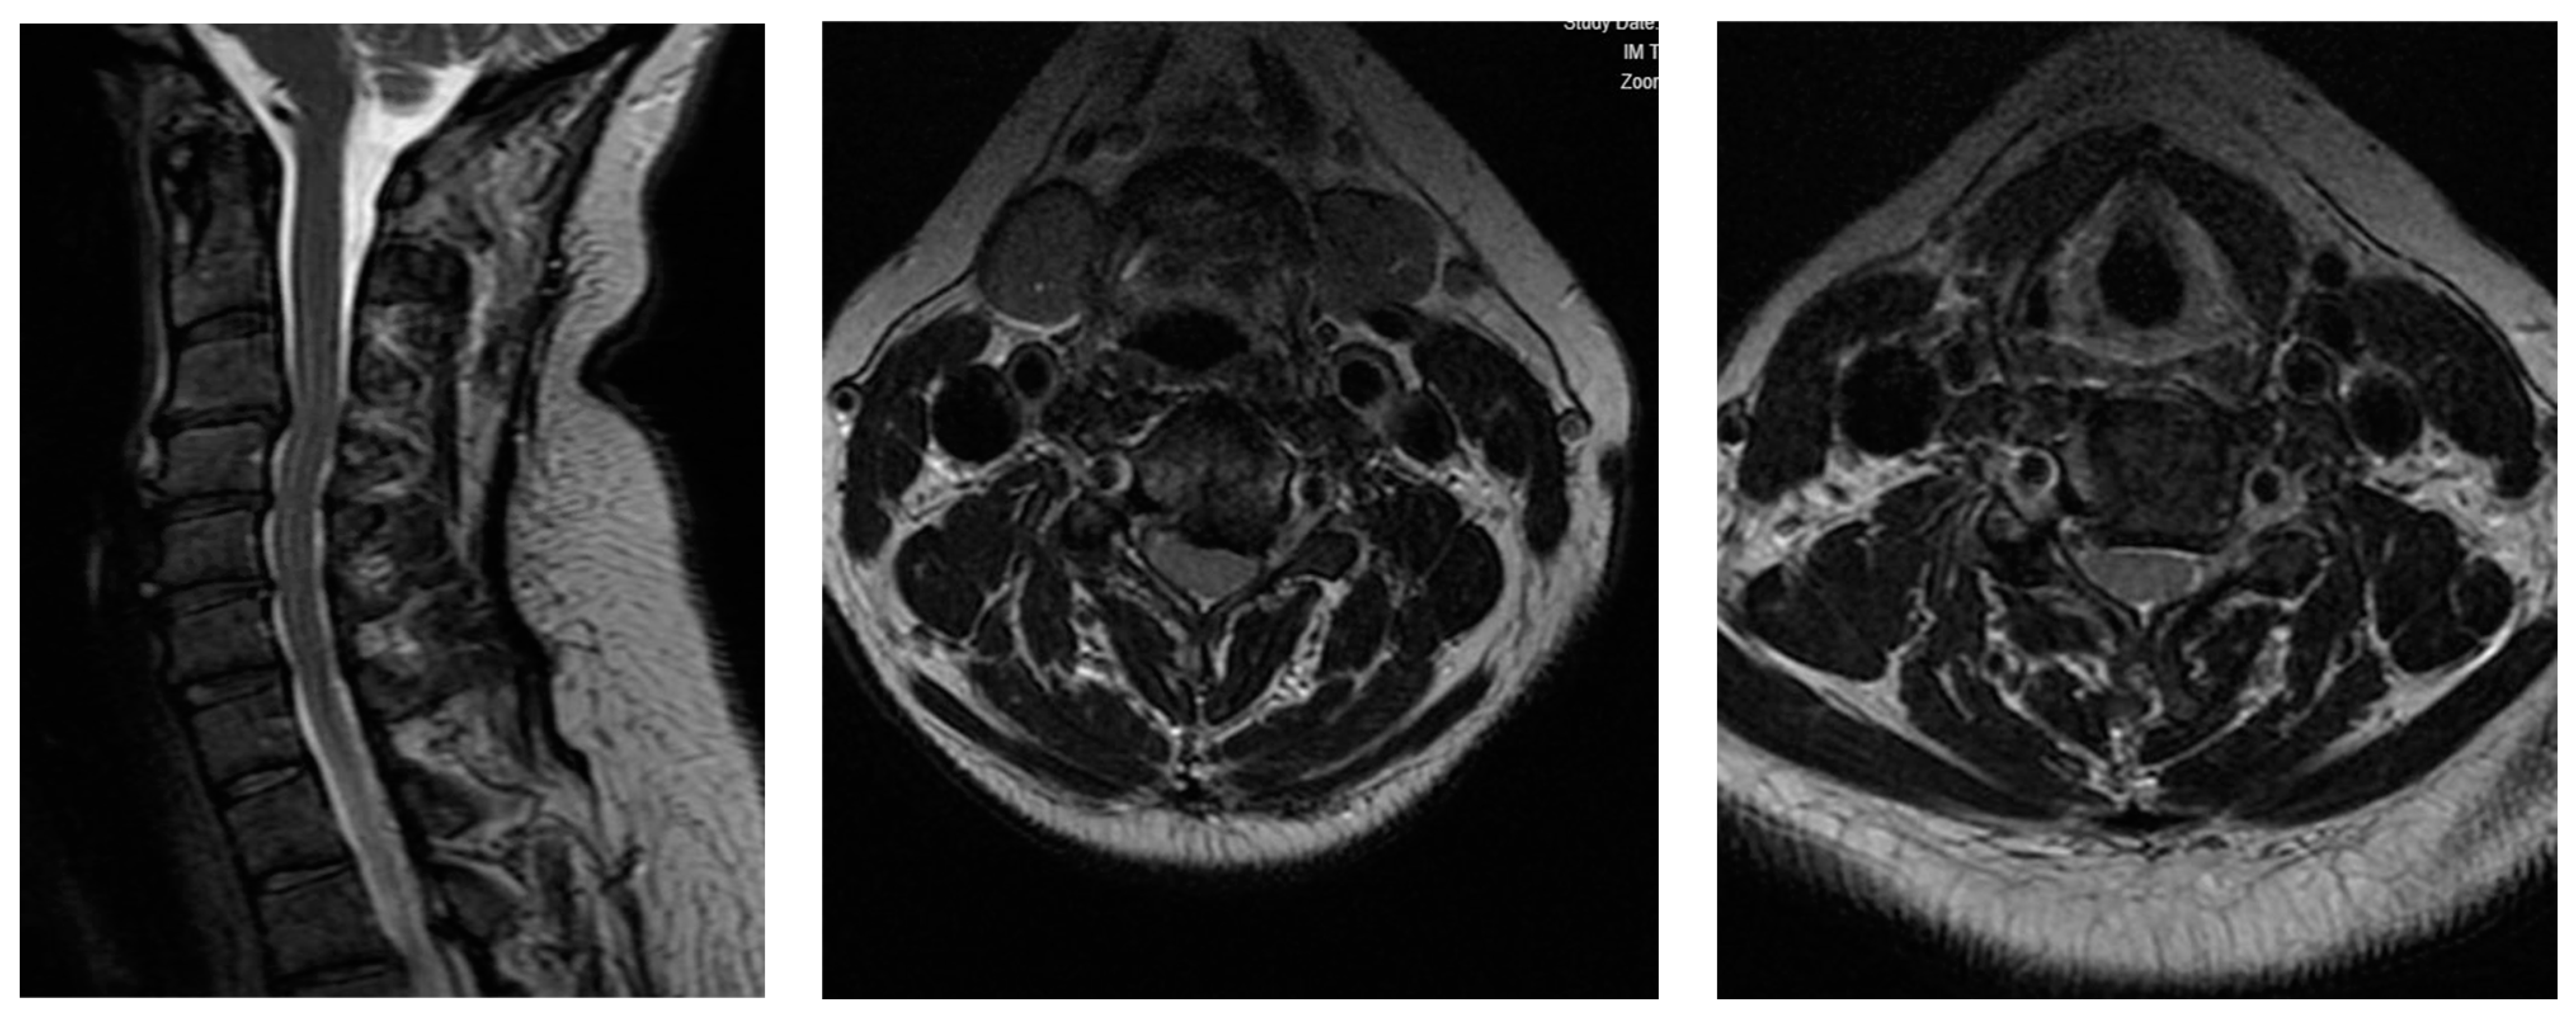

2.2. Case 2